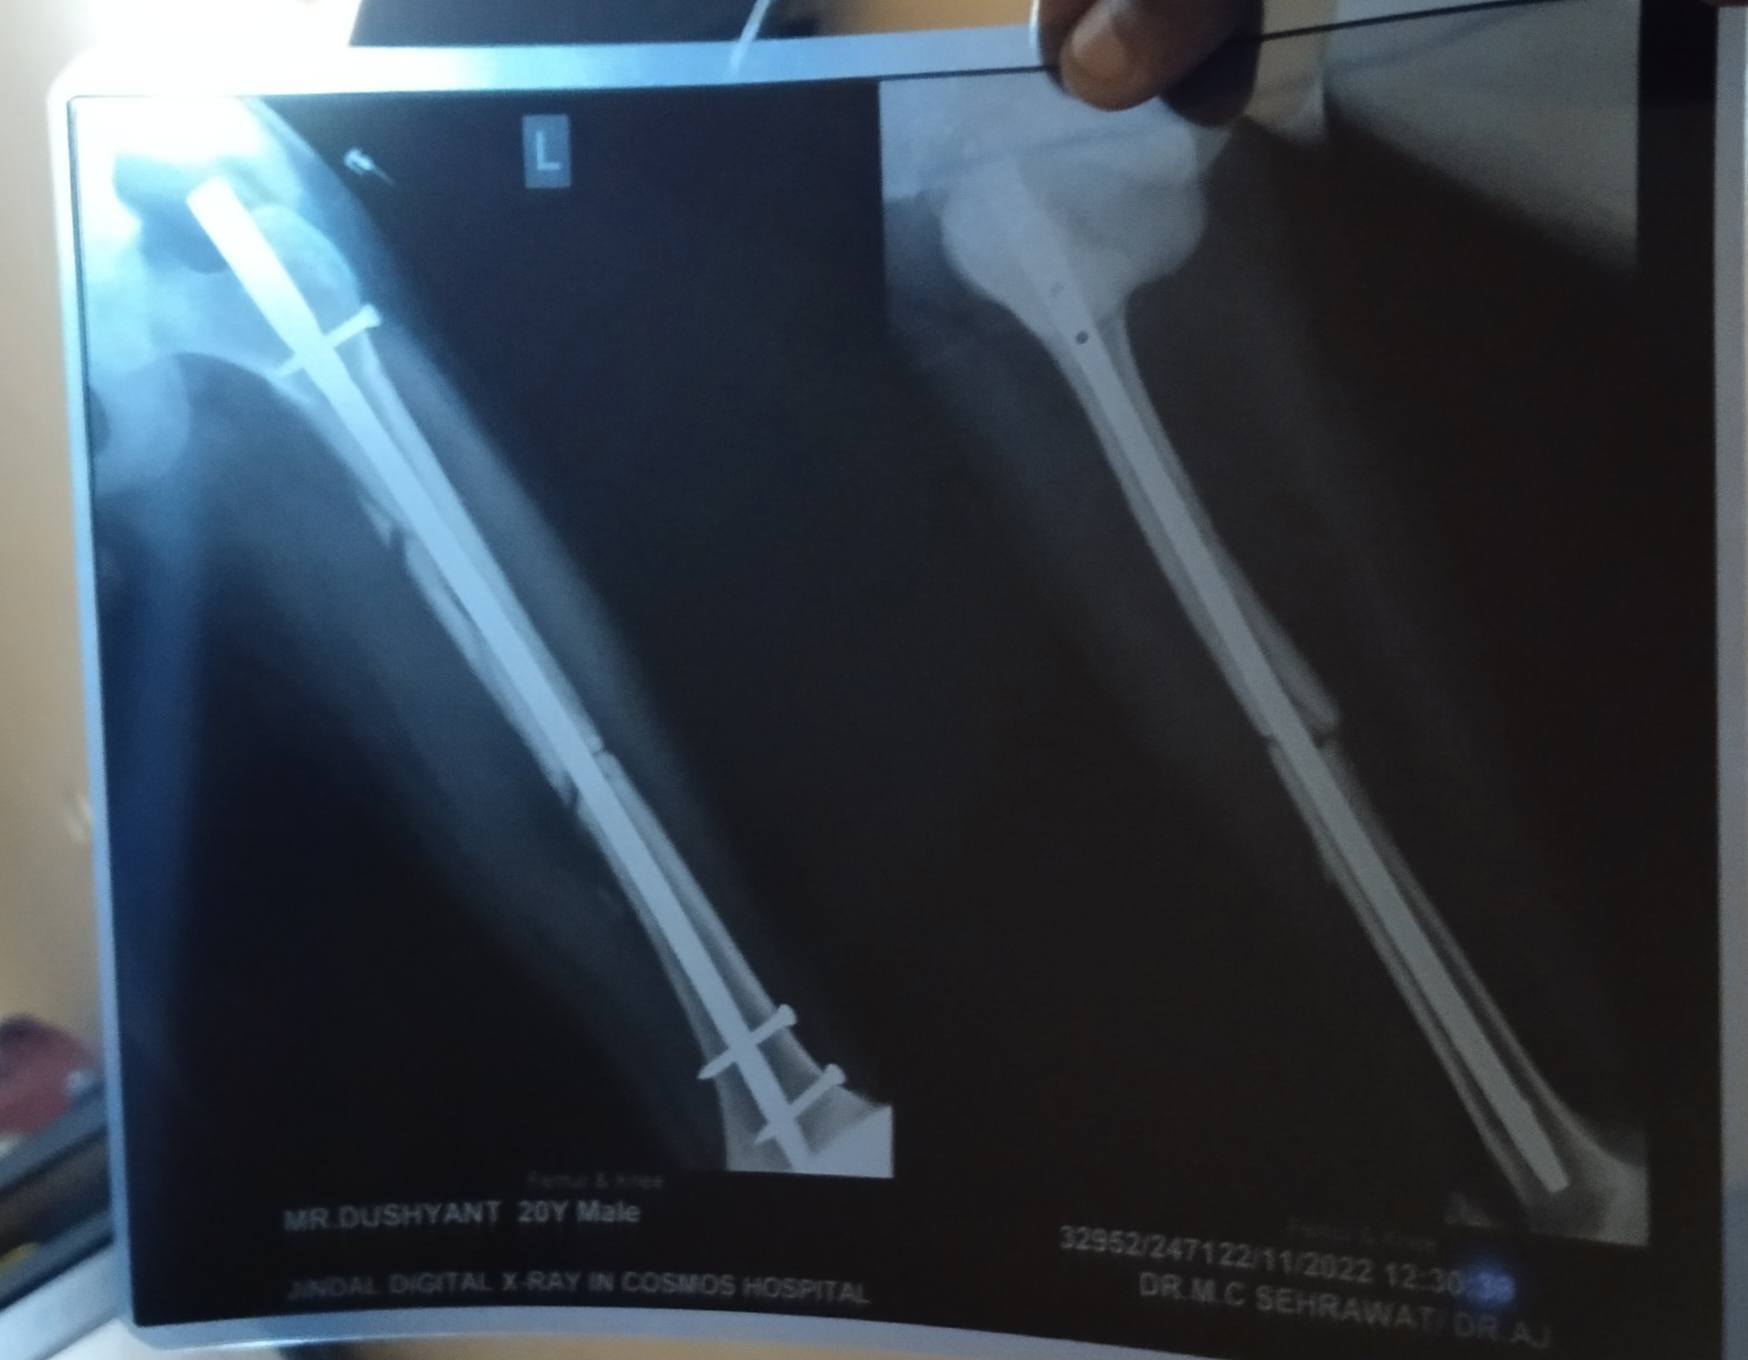

Dushyant from palwal

sir this one is latest x ray of today i have 3 month 12 days left from surgery

will this bone unite either go for bone grafting surgery